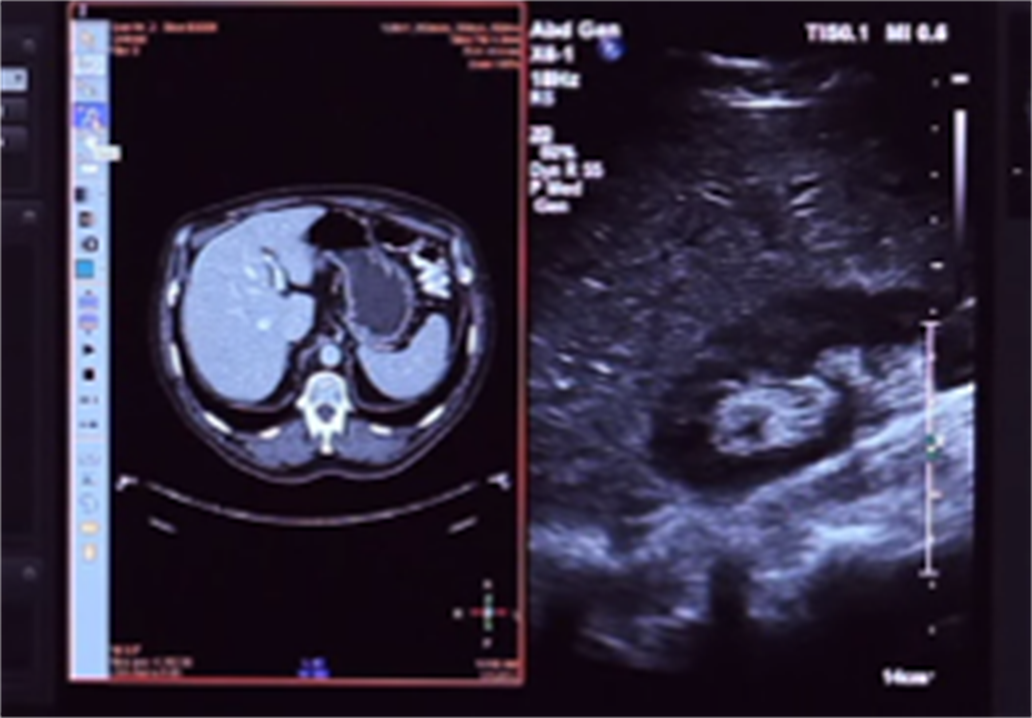

EPIQ7具备联合影像诊断技术。在日常诊断工作中经常需要和其它影像进行对比研究,EPIQ系统可以直接导入多种格式的图像,包括CT,MR,乳房X线,超声图像等;可以无需任何外部软件从EPIQ上调取以前的多种格式图像和超声图像进行对比研究,无论是实时扫描,还是存储的超声图像均可轻松调取多种格式图像进行对比。